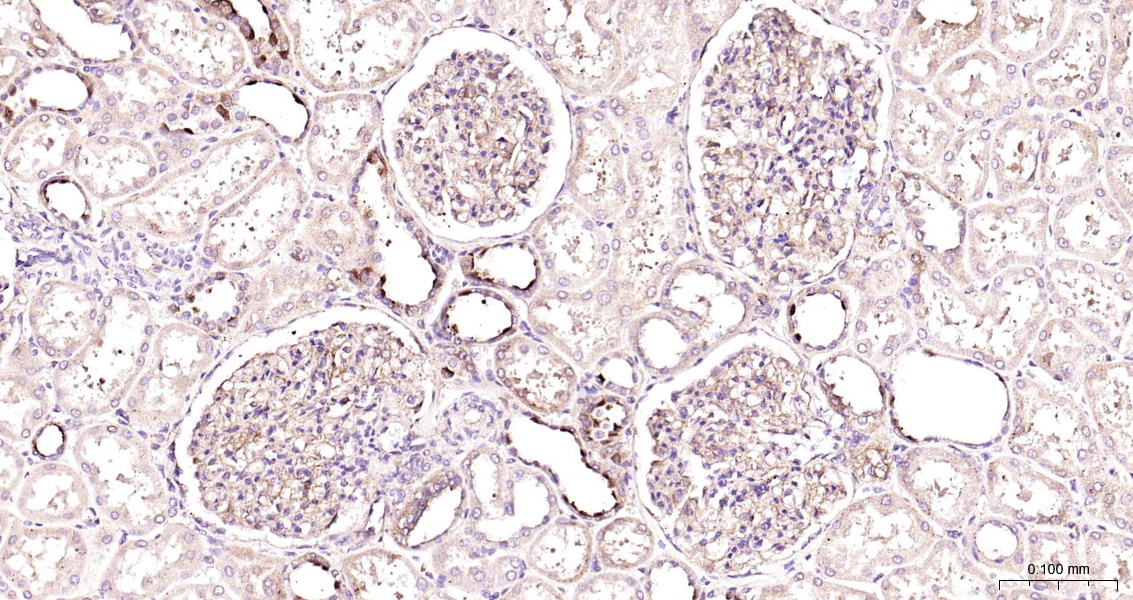

ZO-1 Monoclonal Antibody

Catalog # bsm-41327m

Product Name ZO-1 Monoclonal Antibody

Applications WB, ICC/IF

Reactivity Human

Subcellular location Cytoplasm, Cell membrane

Background The N-terminal may be involved in transducing a signal required for tight junction assembly, while the C-terminal may have specific properties of tight junctions. The alpha domain might be involved in stabilizing junctions. Plays a role in the regulation of cell migration by targeting CDC42BPB to the leading edge of migrating cells.